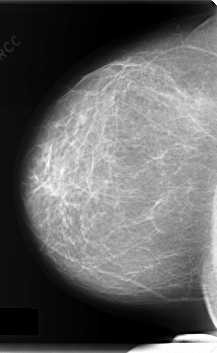

C_0164_1.RIGHT_CC

RIGHT_CC LINES 5992 PIXELS_PER_LINE 3680 BITS_PER_PIXEL 12 RESOLUTION 50 NON_OVERLAY